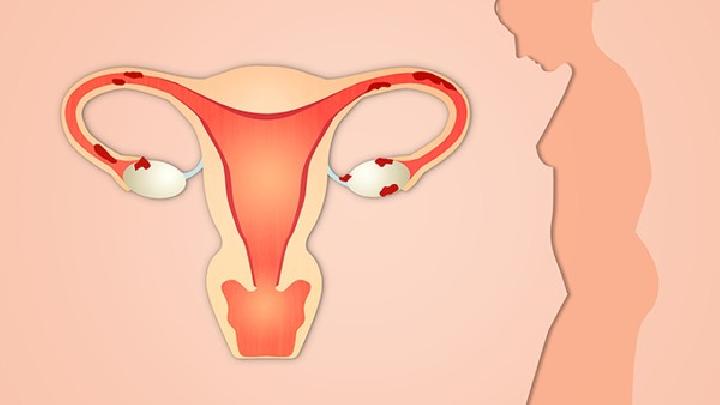

1.局部与远处复发 通常认为,远处转移是再外科手术之禁忌证。但这也不是绝对的,有一些病例可以采用新辅助治疗方法使无法切除的远处转移灶变为可以切除者,同样可以得到再次手术的机会。对存在局部多处复发患者,在有的诊疗中心可进行局部多处病灶的切除术。但因其有较高的手术死亡率,故在不具备手术经验的医院,则不宜勉为其难,可视为手术禁忌证。 对于有症状的局部多处复发患者,一般认为已无法根治性切除。姑息性手术却不能提高生存率,但仅用降低死亡率的观点来评估外科手术切除的疗效是不恰当的。有些姑息性切除可提高患者生活质量和解除其疼痛症状。为解除症状而进行的外科手术治疗只需切除大块复发的肿瘤组织。放疗联合化疗因可以解除疼痛、降低出血、提高生活质量,故通常是姑息性手术术后的常用方法。盆腔血管的选择性化疗对不可切除的肿瘤有减瘤作用。如果复发病灶接近肛门,就需要用腔内支架或结肠造口术。对有出血症状的患者,其他可选择的治疗方法还有激光消融、电烧灼和血管栓塞。局部切除对于会阴复发者,可选择腹会阴联合直肠切除术,但可导致盆腔扩散且预后不良。 3.可切除的局部复发  晚期患者包括盆腔周围侧壁肿瘤浸润、髂血管受累导致下肢水肿、双侧输尿管梗阻导致双侧肾盂积水、坐骨神经受侵犯导致双下肢肌无力、肿瘤侵犯坐骨切迹及腹主动脉周围淋巴结转移等。局限的盆腔侧壁侵犯和S2以上的骶骨侵犯,因为充分切除的可能性很小,被认为是相对禁忌证。 关于切除的信息 子宫切除手术多用于切除子宫肿瘤及某些子宫出血和附件病变等,经腹部切除子宫切除术的操作法,子宫切除术后护理很重要,因为子宫切除术不是一个太小的手术,会对身体造成一定的损伤。  任何手术,包括子宫肌瘤手术都是对患者身体有一定危害的,因此也要尽量避免。是否需要进行子宫肌瘤手术需要根据患者的实际情况来决定,这里我们就简单为您介绍一下吧。  类风湿性关节炎是一种对患者身体危害非常大的疾病,有很多患者因为多年深受这种疾病的折磨从而想到了手术切除,但是这些患者也担心切除后还会复发,所以今天就这个问题我们来了解一下,类风湿性关节炎切除后会复发吗?  女性两侧大阴唇的后面各有一黄豆大小的腺体,该腺体有长约1~2厘米的腺管,开口于小阴唇与处女膜之间的沟内,这个腺体,医学上称为“前庭大腺”。因其生理特点,前庭大腺炎切除病灶后仍然有一定的复发率,因此,保持外阴清洁是预防感染可防止复发的主要方法。  胃癌切除手术后后背经常痛怎么回事?胃癌可能会出现周围组织侵袭和转移的情况,如果出现背部疼痛的情况就要考虑可能和胃癌的脊柱转移有关,针对这种情况要及时到当地医院进行复查,根据转移的情况给予相应的治疗措施,所以胃癌是可以出现背部疼痛的。  前列腺癌睾丸切除手术多少钱,很多肿瘤晚期都会发生转移,前列腺癌也不例外。约有三分之一甚至三分之二的前列腺癌患者在初次就医时就已有淋巴结转移,多发生在骼内、骼外、腰部、腹股沟等部位。可引起相应部位的淋巴结肿大及下肢肿胀。血行转移多见于骨骼(如骨盆、骶骨、腰椎、股骨上段等〉和内脏(如肺、肝、脑、肾上腺、睾丸等)。所以患病就要及时治疗,但是很多人不知道前列腺癌治疗要花多少钱,下面就由小编详细的为您介绍,前列腺癌睾丸切除手术多少钱。  骨癌切除后还会复发吗?部分骨癌患者在手术后还会出现病情恶化或者复发的情况,患者很不明白这是怎么回事,骨癌复发对人体的危害很大,因此要注意预防,这对治疗效果有很大的帮助,而且还能让患者摆脱骨癌的困扰,和正常人一样生活。  近几年胆囊息肉的患者越来越多,据临床统计显示,其中产生癌变的大约有12%,所以为了预防胆囊息肉发生癌变,患者们一定要积极进行治疗。目前胆囊息肉最有效的治疗方法当属手术治疗,手术可分为保胆取息和胆囊切除两种方式,由于胆囊切除多少会对身体产生一些不利影响,并且不是所有患者都需要行胆囊切除术,因此患者们一定要三思而后行。  有时候,人们在进行疾病治疗方面,对于引起该类疾病的原因是模糊的,因此在治疗方面不能很好地展开。对于子宫肌瘤此类常见妇科疾病,广大女性朋友也不是很清楚其病因,在治疗方面也是比较困难的,下面小编就为大家介绍子宫肌瘤是怎么引起的?  肝癌是如今世界上对人类健康危害最大的恶性肿瘤之一,对于早期肝癌病人和病人家属来说,希望明确的第一个问题就是:肝癌早期切除后能治愈吗?就目前治疗现状而言,肝癌仍然是医学上未被攻克的一大难题,然而这也并不等于得了肝癌就被宣判了死刑,临床上亦有许多治疗后长期生存的病例。 |